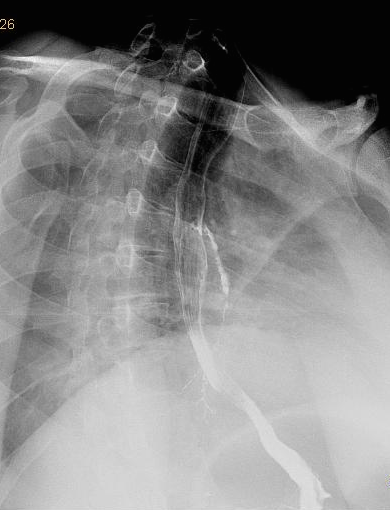

Um welche Diagnose handelt es sich?Junge Frau, Emigrantin, seit Jahren Husten, rez. Infekte -

traut sich niemand eine verdachtsdiagnose zu stellen? die lösung ist nicht leicht, aber klinisch sehr relevant. ich habe auch zur erleichterung ein literaturangabe gemacht.